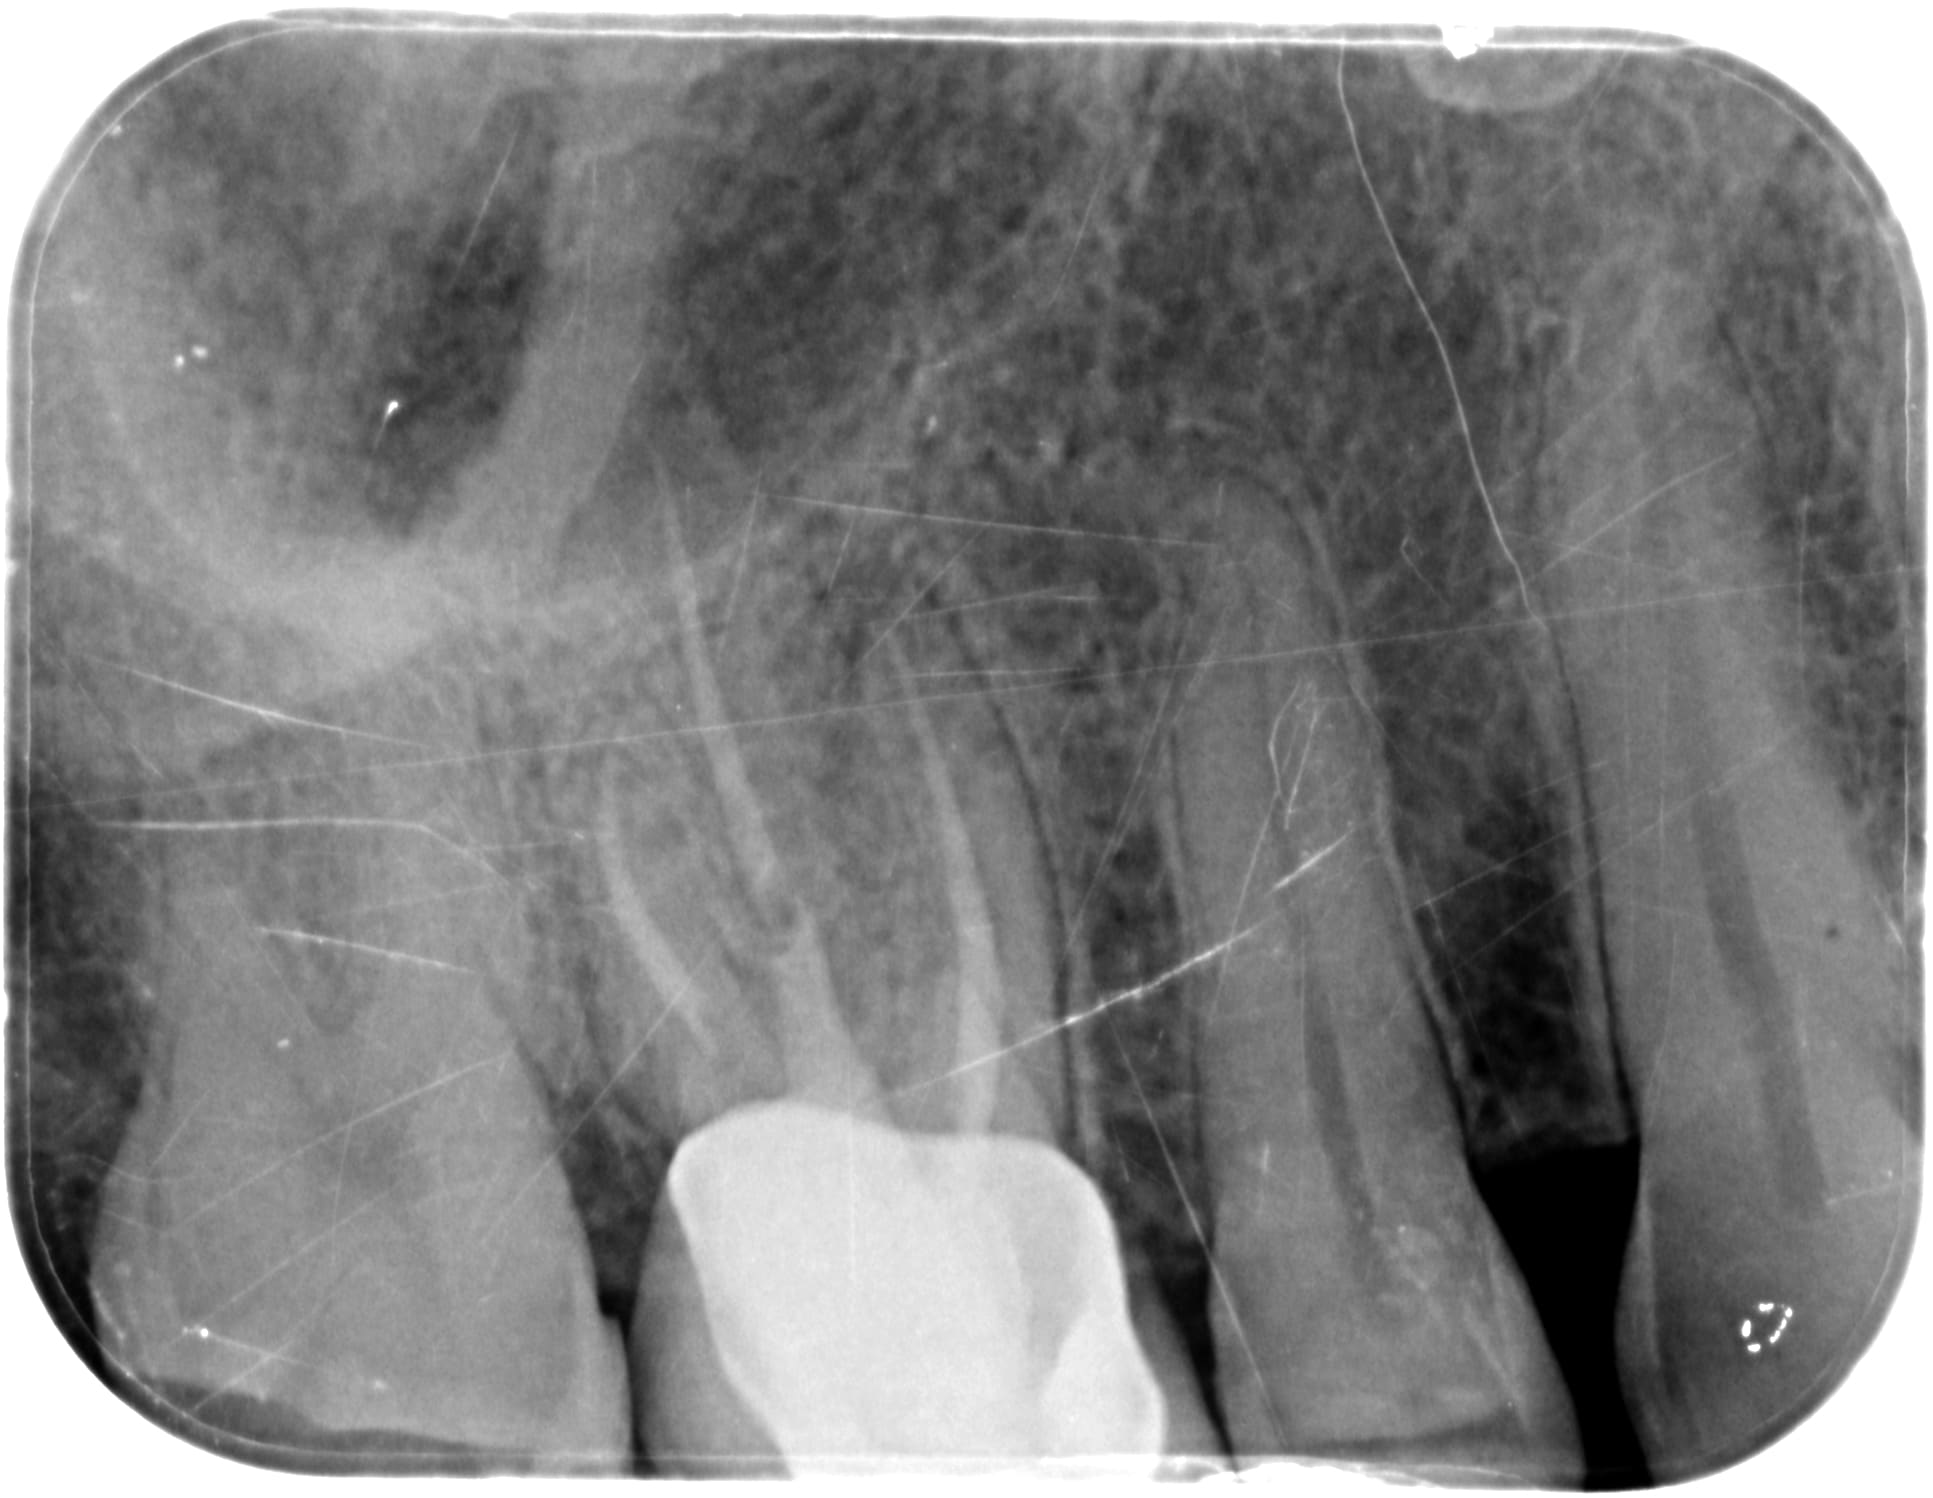

C'était le mv2 que je n'avais pas trouvé et qui s'était infecté.

Par contre, j espère que tu as une radio per OP crampon en place... Sinon c est une faute. Et la c est une autre histoire.

OP a mis la digue mais se disant que avec reciproc et localisateur d'apex il n'avait pas besoin de radio per op.